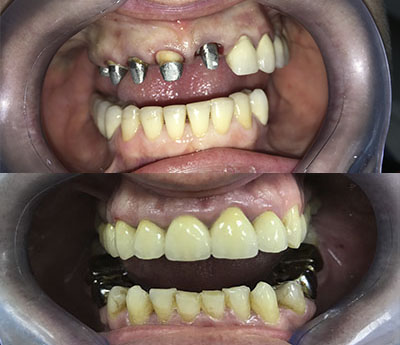

O asemenea piesă protetică restaurează integritatea arcadelor dentare. Proteza mobilă realizată corect va ameliora estetic trăsătura feței pacientului, va permite restabilirea funcției masticatorii și va îmbunătăți fonația.